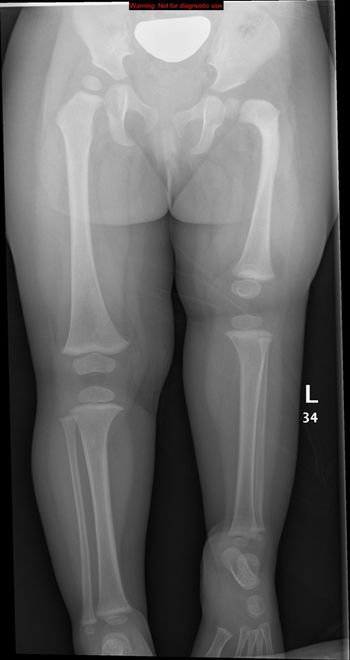

Newborn baby with short left lower limb with appearance of proximal femoral focal deficiency. Femur is shortened, flexed, abducted, and externally rotated.